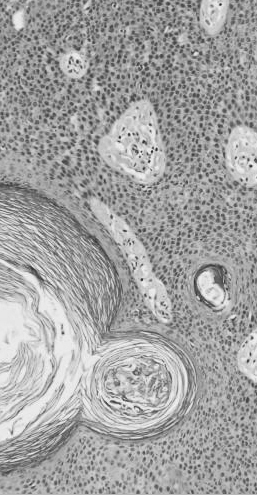

Dermatopathologie bei Mainz

Unsere Praxis ist 1992 von Priv-Doz. Dr. med. Böckers

in Nieder-Olm bei Mainz gegründet worden und

stellt seitdem eines der bedeutendsten von Dermatologen geführten Praxen

für die histopathologische Begutachtung von Hautpräparaten in

Rheinland-Pfalz dar. Wir